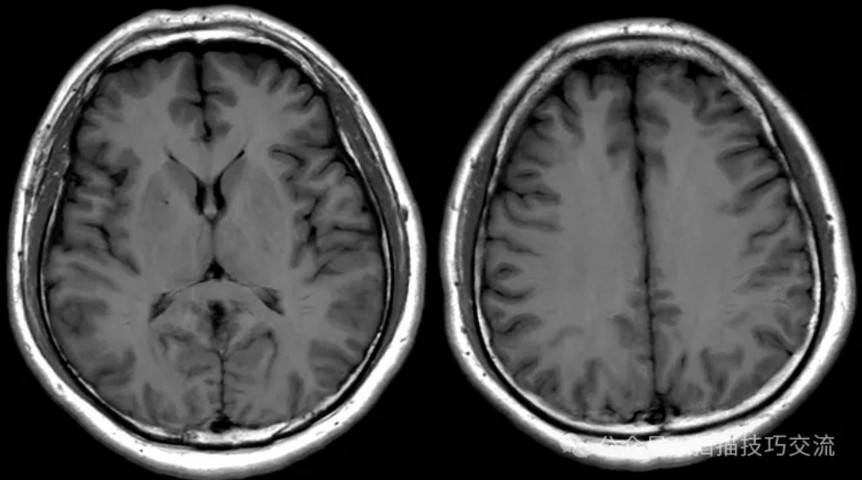

颅内静脉黑血成像,CUBE T1fs w/o +c,静脉窦未见异常。